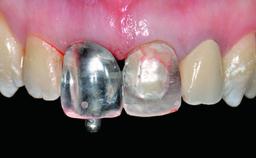

Replacement of a Missing Upper Left Central Incisor: Late Placement of an RC Bone Level Implant, CAD/CAM Zirconia Abutment

Abutment Type CAD/CAM

Prosthesis Type FDP

Retention Cemented, with prosthesis margin < 3mm submucosal Cemented, with prosthesis margin < 3mm submucosal

Provisional Implant-Supported Prosthesis Prosthodontic margin > 3 mm apical to mucosal margin Prosthodontic margin > 3 mm apical to mucosal margin